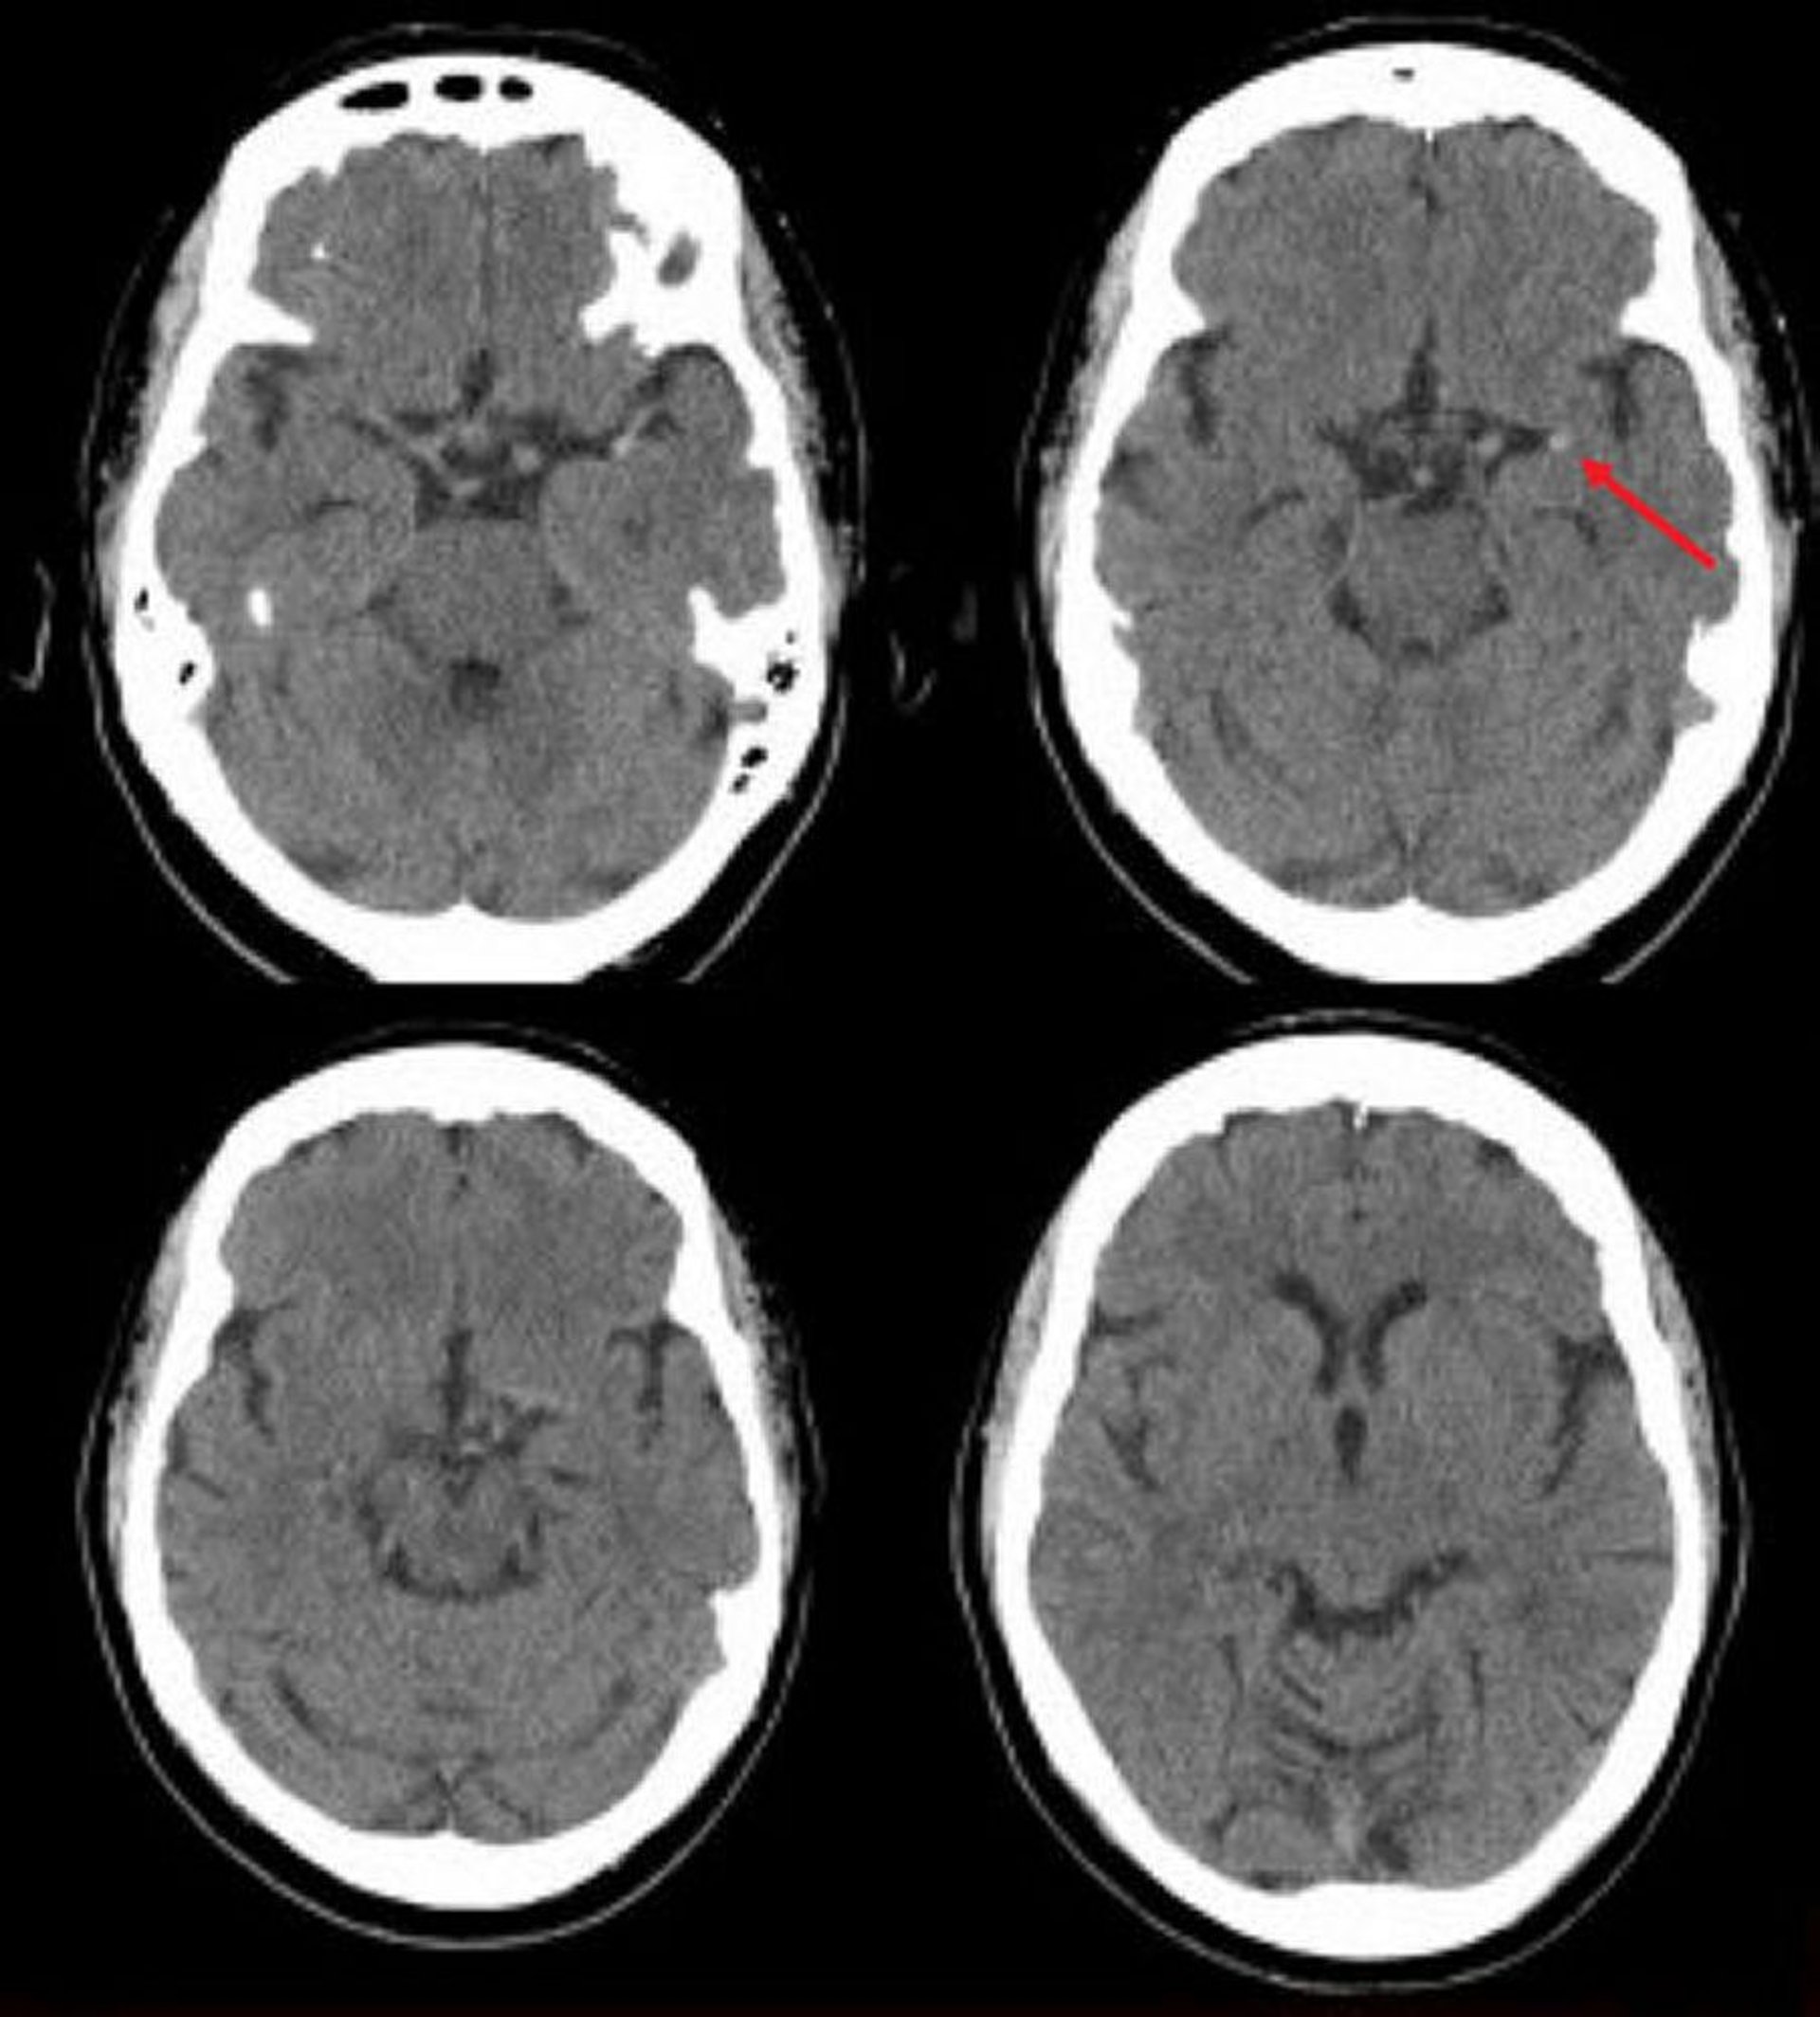

Ictus ischemico nell'arteria cerebrale media sinistra (TC)

Questa scansione TC cerebrale senza contrasto mostra un'arteria cerebrale media sinistra iperdensa. Questo risultato indica un coagulo focale nell'arteria cerebrale media sinistra (freccia).